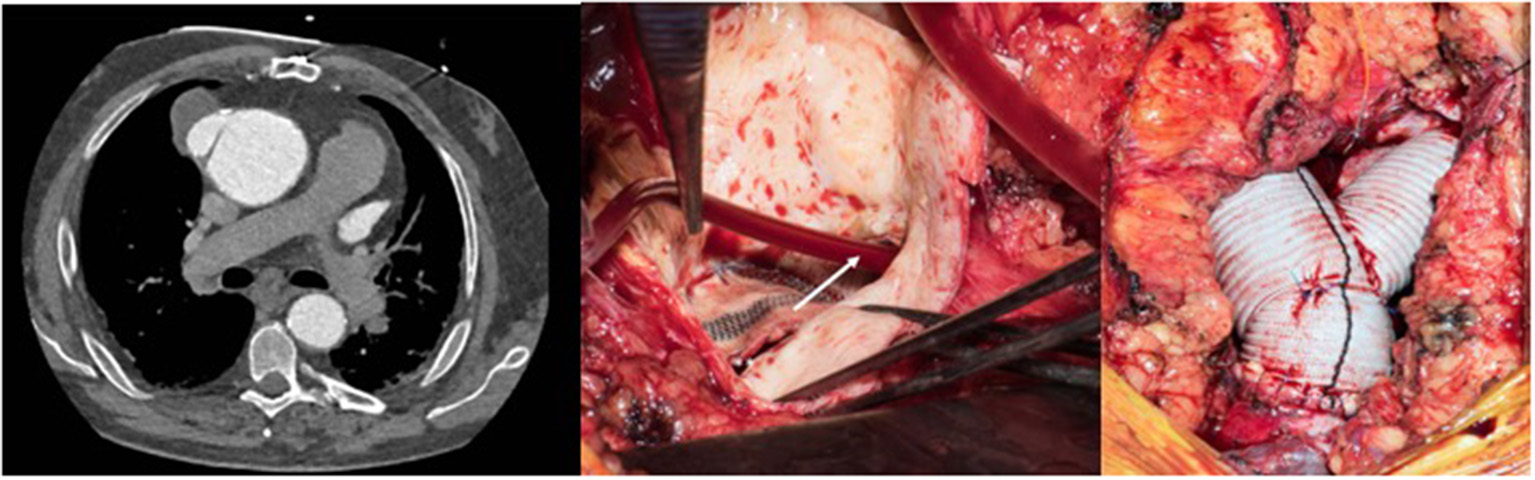

A 23-year old female was referred because of hemoptysis. She had had aortic coarctation repair with a prosthetic patch at the age of 6. Eight years later an ascending-descending bypass was performed because of re-coarctation. At admission, she presented with an ascending aortic aneurysm and a large pseudoaneurysm at the distal anastomosis of the previous extra-anatomic bypass that was itself partially thrombosed. The proximal descending aorta was highly narrowed (Figure 10). A small peripheral aorto-bronchial fistula was suspected as cause of the hemoptysis because it could not be identified during bronchoscopy. Operative repair was performed under double arterial canulation (aortic for the upper body and femoral artery for the lower body perfusion). The procedure was performed through mid-sternotomy and left hemi-clamshell and consisted in double ligation of the descending aorta proximally and distally of the end-to-side previous bypass anastomosis in order to exclude the pseudo-aneurysm. The ascending aortic aneurysm was resected and the aorta replaced with a prosthetic vascular graft and finally, an ascending-descending bypass was performed to restore continuity between the ascending with the distal descending aorta (Figure 11). The suspected site of the aorto-bronchial fistula was addressed by a small wedge-resection and the suture line covered with a intercostal muscle flap. Postoperative recovery was uneventful.

Figure 11

Intraoperative view following replacement of the ascending aorta and ascending-descending bypass implanted laterally in the ascending aortic graft. Reproduced with permission from Ann Thorac Surg. 2008; 85:460–4.

The second case was a 28-year old female who was operated at the age of 10 years and received a patch enlargement as a treatment of aortic coarctation. She did well until the age of 27 when a large pseudo-aneurysm was suspected incidentally on a chest x-ray performed for pulmonary reasons and confirmed by CT-scan. This picture showed in a certain way the challenges of planning surgery with rather simple imaging possibilities in emerging countries. Re-operation was indicated and performed through a lateral thoracotomy under femoro-left atrial bypass and moderate hypothermia (28°C) since a safe clamping of the proximal descending aorta was expected to be difficult. In fact, the aneurysm originated from the suture line of the patch with the native aorta and covered the whole proximal third of the descending aorta. Once the targeted core temperature was reached, the bypass was stopped and the aneurysm opened. Since the period of circulatory arrest was not expected to be prolonged, no additional cerebral protection was planned. Replacement of the proximal descending aorta was performed with the proximal suture line at the level of the left subclavian artery in the open arch technique (circulatory arrest time 14 min) and the distal one at the mid-level of the descending aorta. The vascular graft was approximately 10 cm in length. Weaning from cardiopulmonary bypass was difficult because of a coagulopathy and severe oozing though the graft but inclusion using a pericardial patch allowed the situation to be controlled. The patient was extubated on postoperative day 2. Unfortunately, she had severe pulmonary problems a week later and had to be re-intubated, but unfortunately died 10 days after surgery from respiratory failure.